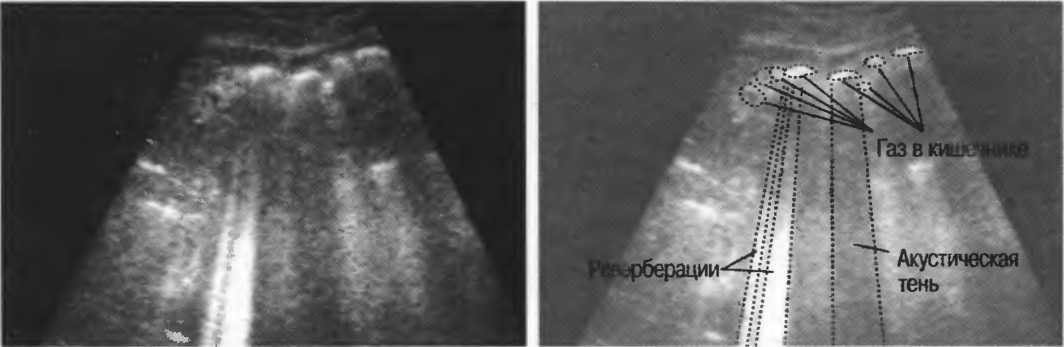

Газ в кишечнике или еще где-либо вызывает появление различных эхографических феноменов. Ультразвуковой луч может рассеиваться, отражаться, поглощаться и преломляться таким образом, что становится практически невозможной визуализация подлежащих структур. По этой причине ультразвук не может быть использован для визуализации нормальных легких или выявления заболевания легких, за исключением объемных процессов, расположенных по периферии органа. Рентгенография грудной клетки в этом случае даст большую информацию.

Плотные материалы, такие как кости или камни, дают акустическую тень на структуры, расположенные сзади, в результате того что ультразвуковая волна не проходит через них. Этот феномен получил название «акустической тени». Например, ребра могут экранировать ультразвуковой поток, поэтому структуры, расположенные за ними, нужно исследовать в косом направлении по межреберным промежуткам (рис. 10б,в).

Реверберации имеют место при прохождении ультразвукового луча от одного вида ткани к другому при резко выраженном различии акустического сопротивления этих тканей, например от кишечного газа к печени или ребрам: реверберации могут экранировать ткани, лежащие за газом (рис. 20а).